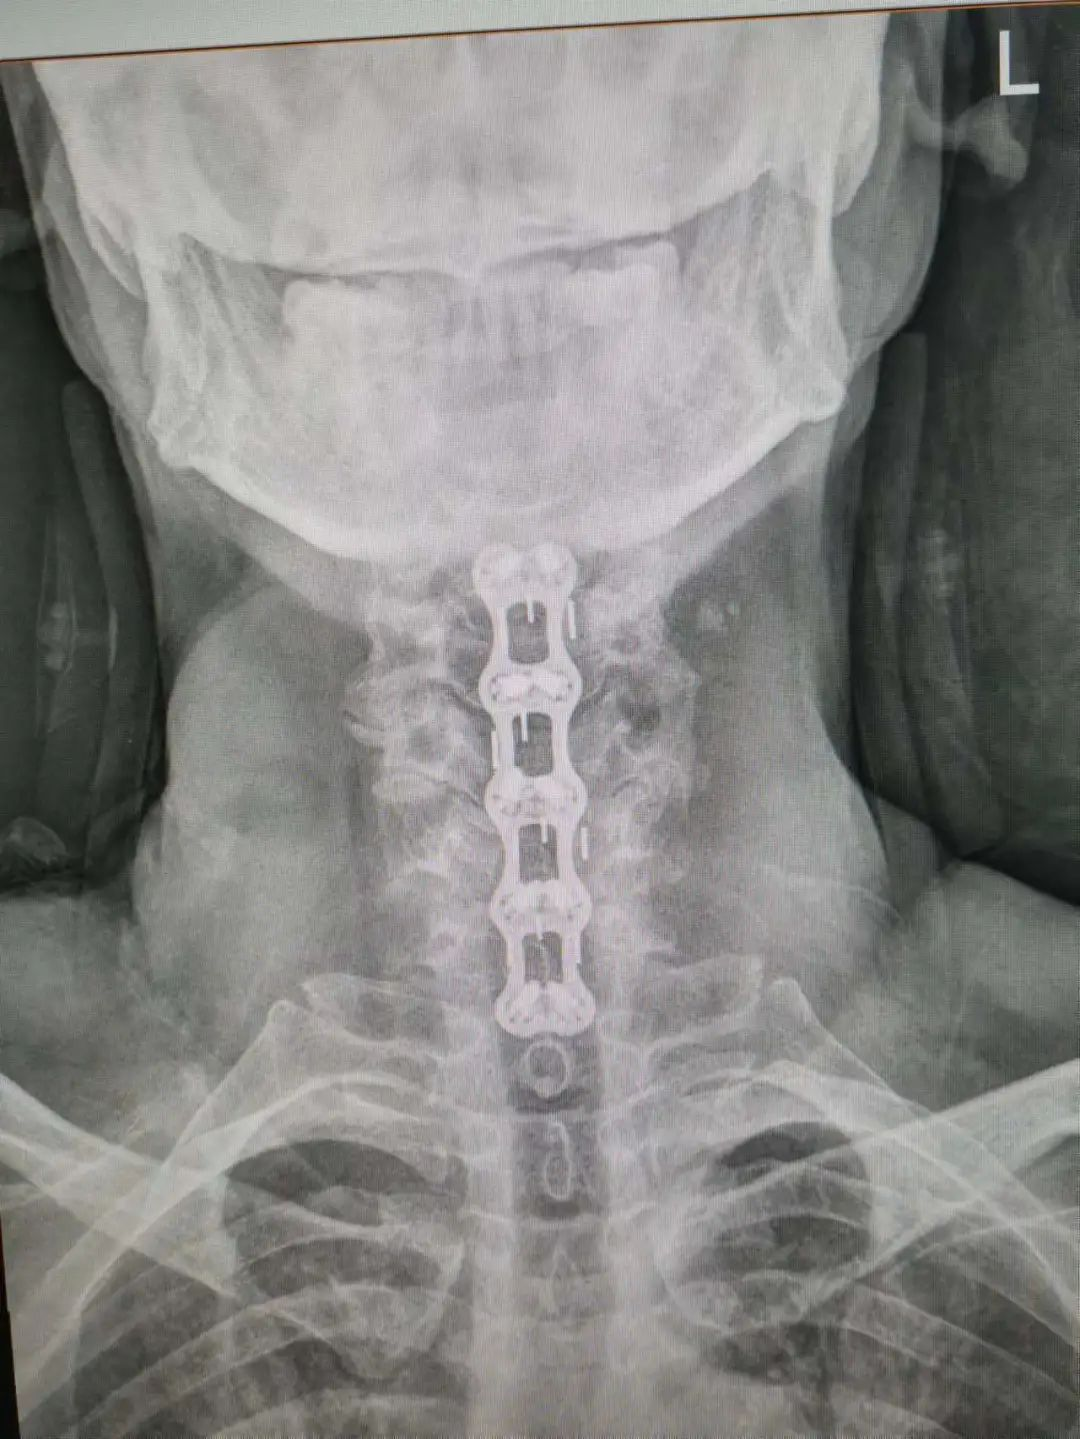

楊先生術(shù)后拍片

由于楊先生的病情嚴重,需住院治療。楊先生入院后,瀘州市中醫(yī)醫(yī)院骨傷二科科主任楊陳一制定了手術(shù)計劃,決定脊髓型頸椎病的手術(shù)從前路切開減壓,頸3/4 、頸4/5、 頸5/6、 頸6/7椎間盤切除,椎間融合,鋼板內(nèi)固定術(shù)手術(shù),而腰椎管狹窄癥經(jīng)后路切開減壓,腰3/4、腰4/5椎同盤動除,椎間融合、釘棒系統(tǒng)內(nèi)固定術(shù)。